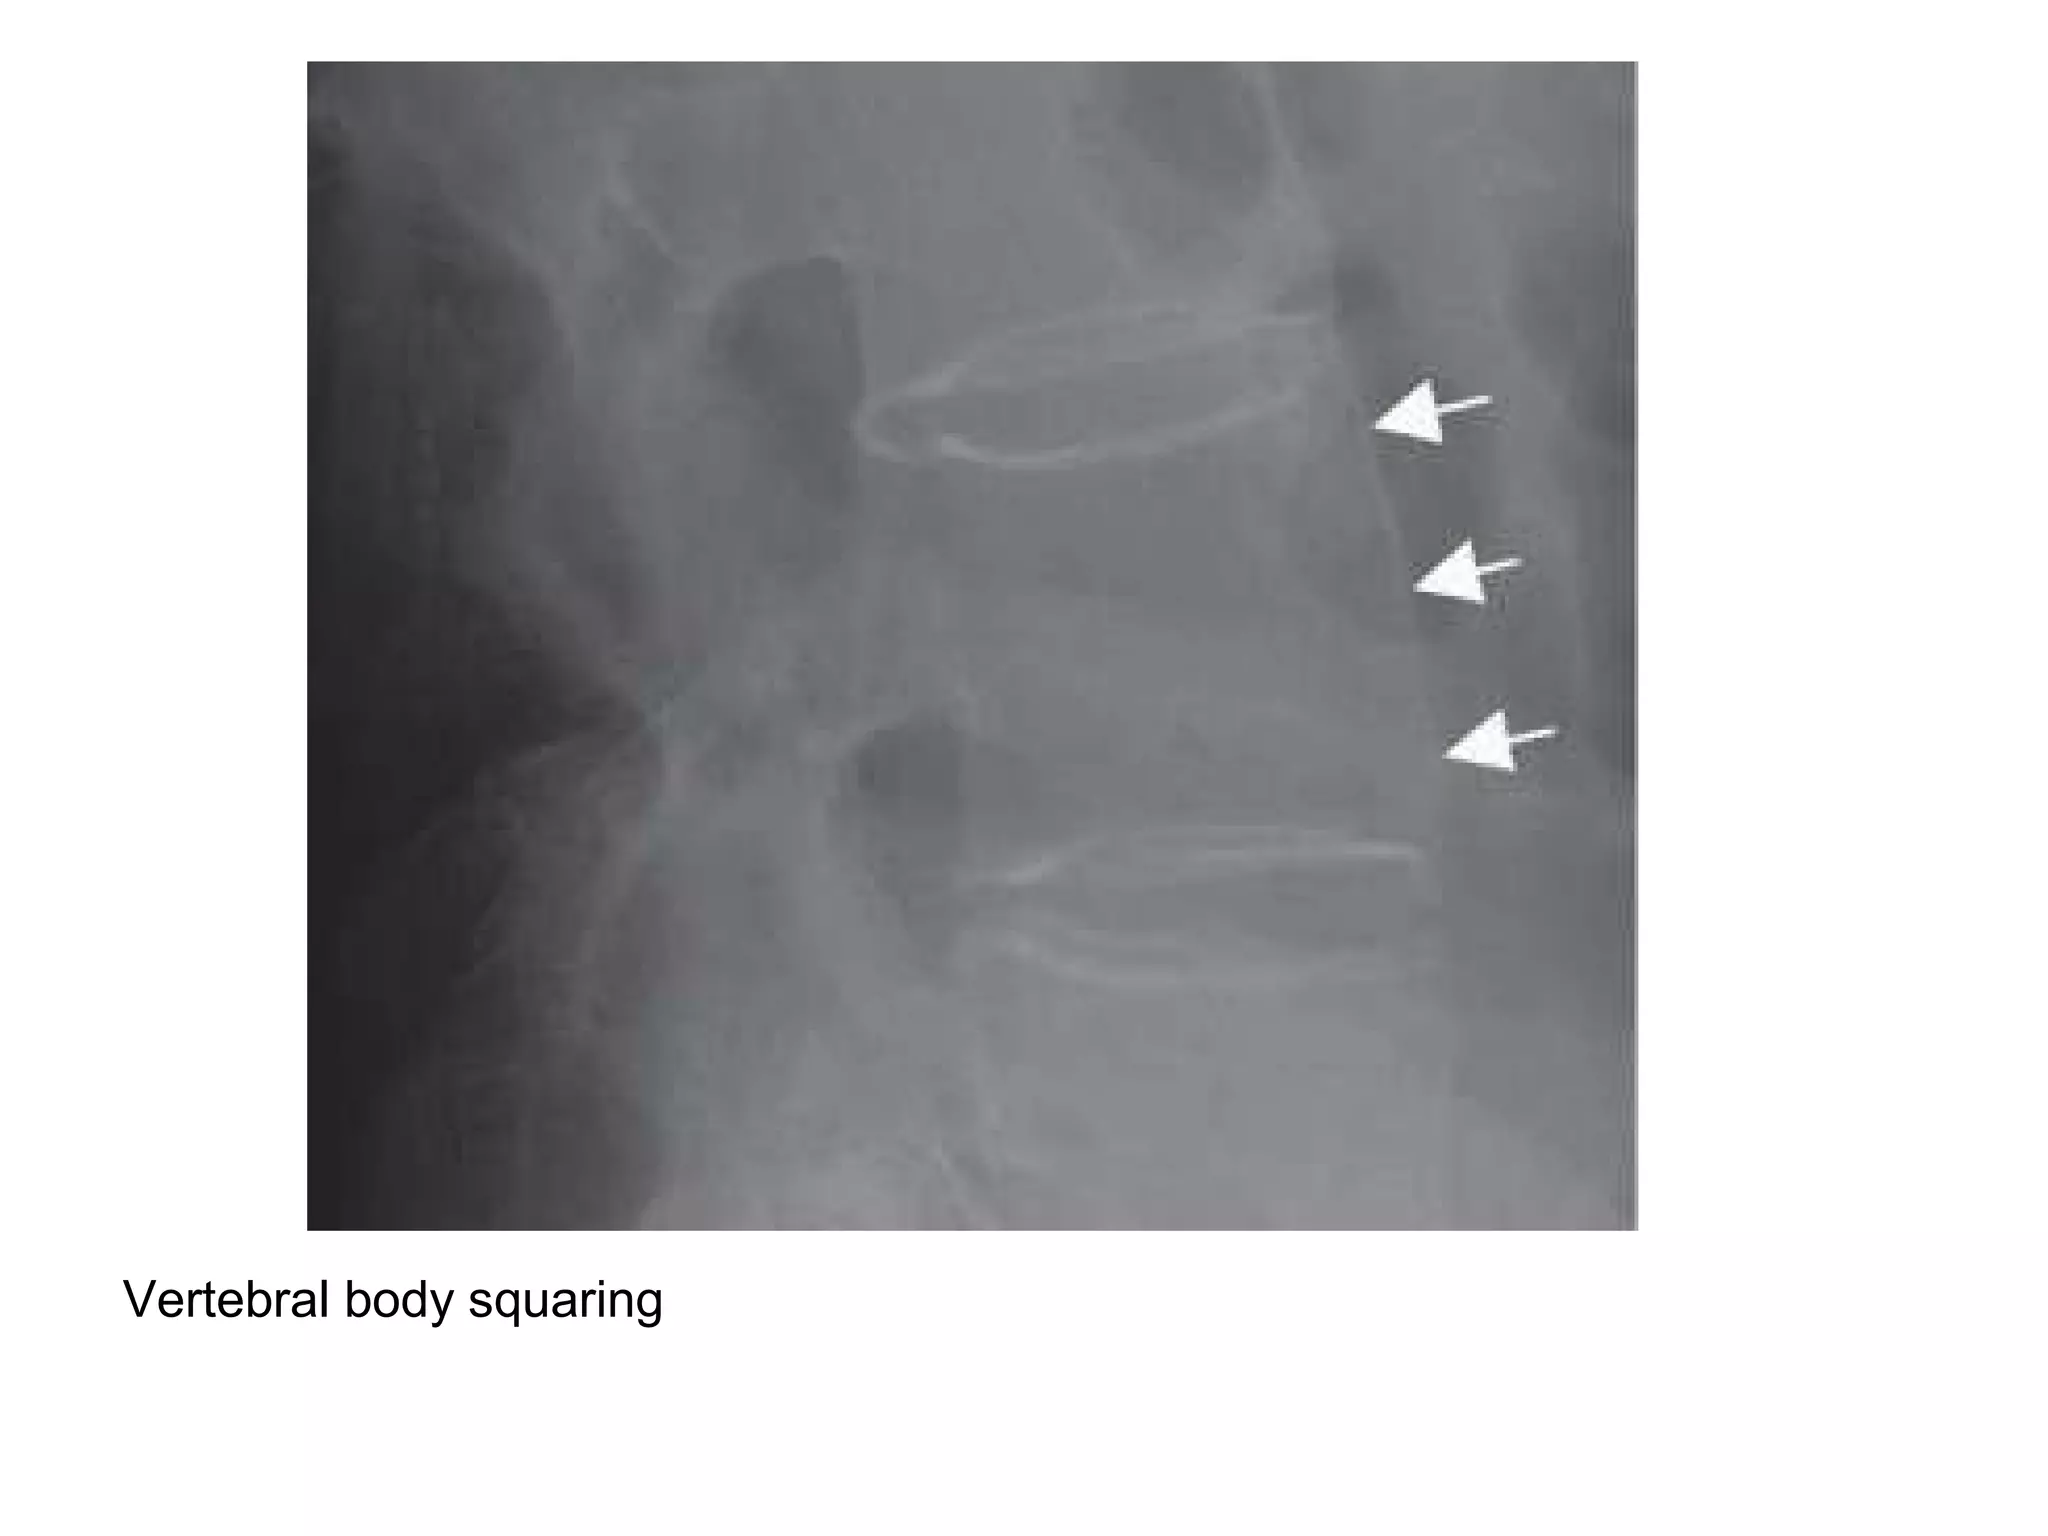

2-Vertebral body squaring :

-Refers to loss of normal concavity of the anterior

border

Vertebral body squaring

Vertebral body squaring , lateral radiograph shows squaring of L3 and

L4 vertebral bodies , L3-L4 anterior syndesmophyte and lumbar

facet joint fusion